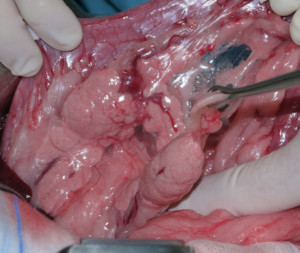

La cirugía de elección es la pancreatectomía parcial y la resección de losnódulos linfáticos (NNLL) centinelas (imágenes 3A-3I). La quimioterapia intracavitaria puede controlar la efusión por carcinomatosis secundaria, pero ofrece una respuesta paliativa de corta duración. La pancreatectomía completa o pancreaticoduodenectomía (técnica de Whipple), descritas en el perro, presentan altas tasas de morbilidad y mortalidad operatorias. La técnica de Billroth II es una opción paliativa a corto plazo en casos de obstrucción intestinal. En un estudio retrospectivo en 34 pacientes felinos con carcinoma pancreático exocrino primario la enfermedad se asoció con una historia previa de diabetes mellitus.35 El carcinoma pancreático exocrino canino se caracteriza por una alta tasa de metástasis y un pronóstico grave general.37

Imágenes 3A – 3I. Secuencia de imágenes quirúrgicas en un perro (con las imágenes del TC), durante una pancreatectomía parcial del lóbulo izquierdo y cuerpo del páncreas, usando un sellador vascular/tisular, por carcinoma pancreático.